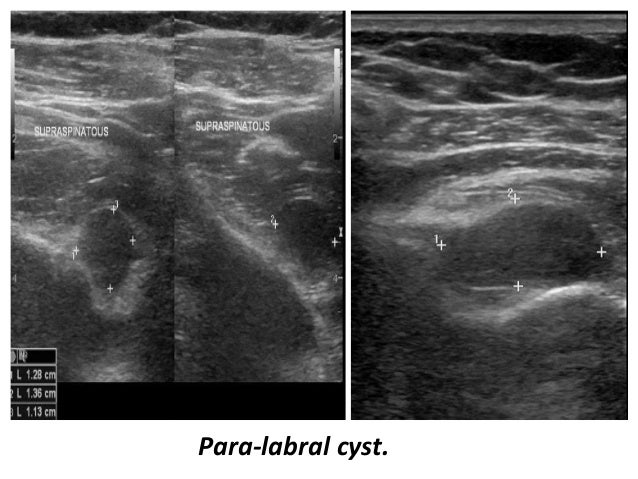

50. 50. Para-labral cyst.